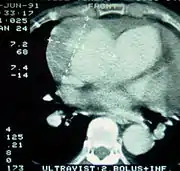

![]() |

| Computed tomography (CT) | Legend |

| Disección aórtica tipo A de Stanford 1 aorta ascendente, cierto Lumen - 2 Lumen falsa - 3 arteria pulmonar 4 aorta torácica descendente - 5 vértebra torácica | |

La Angiografía de Tórax por Tomografía Computarizada (Angio-TC de Tórax) es una prueba no invasiva de rápido acceso cuyo objetivo es dar una vista tridimensional de la aorta. Estas imágenes son producidas rápidamente, teniendo que cortar rebanadas delgadas del pecho y el abdomen, combinados en el ordenador para crear la sección transversal. A fin de delinear la aorta a la precisión necesaria para hacer el diagnóstico correcto, un material de contraste yodado se inyecta en una vena periférica. El contraste es inyectado y el análisis realizado utilizando un método de seguimiento.

Corresponde al Gold Standard para el diagnóstico de Disección Aórtica, con una sensibilidad de 96 - 100% y una especificidad de 96 a 100%. Las desventajas incluyen la necesidad de material de contraste yodado y la necesidad de estar disponible en un centro asistencial de alta complejidad.